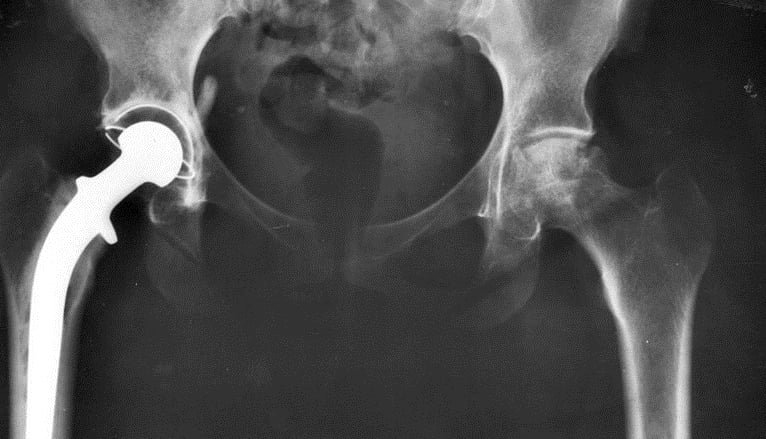

Hip Joint Infection

A hip infection happens when germs get into the bone or joint and reproduce. Viruses, bacteria, fungi and parasites can all cause infections. Our skin normally has bacteria on it. It is these germs that most often cause infections in the bones and joints.